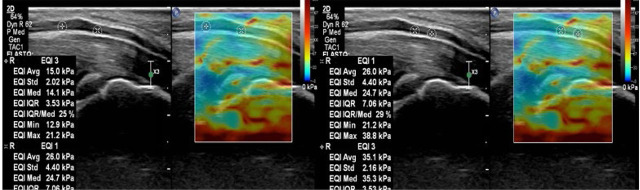

Elastografía en paciente con síndrome del túnel del carpo moderado

En cuanto a la SWE, el parámetro más sólido fue el valor dentro del túnel, con una especificidad del 100% y una sensibilidad del 88%. Un punto de corte de ≥63.5 kPa ofreció un rendimiento diagnóstico del 94% (AUROC: 0.957).

La combinación de SWE con CSA aumentó notablemente la precisión, alcanzando una exactitud del 98% dentro del túnel (AUROC: 0.995). Incluso fuera del túnel, donde cada parámetro por separado tenía menor capacidad predictiva, su combinación mejoró sustancialmente la utilidad clínica.